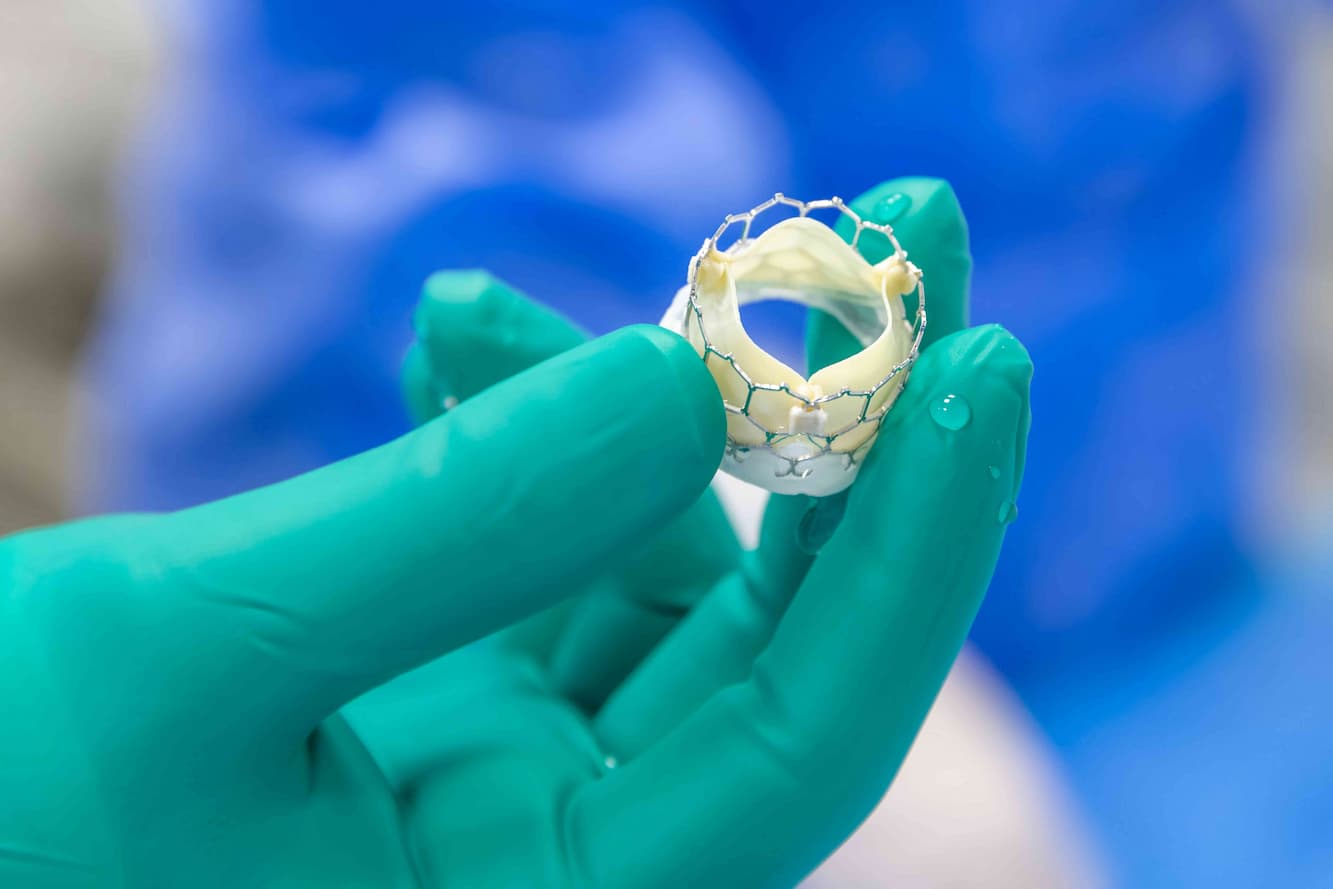

Cardiology plays a pivotal role in maintaining heart health, covering everything from regular check-ups to complex procedures. We partner with esteemed cardiologists from top hospitals.

Cardiology plays a pivotal role in maintaining heart health, covering everything from regular check-ups to complex procedures. We partner with esteemed cardiologists from top hospitals.